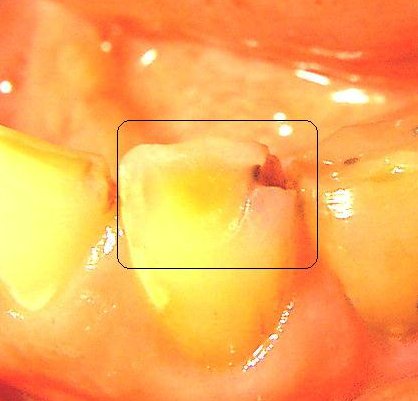

9:30 a.m. Early this past spring, the dentist had to put a peg in a tooth that is two teeth to the left of my front ones. And he rebuilt the upper part of the tooth; this lasted for only a month. The area he fixed broke. It also took a sizable piece of good tooth with it, leaving the upper part of the peg exposed. It took a good two months or so for it to stop being so sensitive to hot and cold, and when brushing my teeth. If I werent careful, once in awhile it would give my tongue a good sharp poke while eating. This morning while brushing my teeth I noticed that the peg is disappearing. I can't see where it goes down into the tooth so much now and there is new tooth growth over the top of this peg!!

Broken tooth on 10-9-2000

Broken tooth on 11-11-2000

Broken tooth on 12-29-2000

Broken tooth on 1-8-2001

The other cavity that I mentioned earlier in this diary, that is to the right of my two front teeth is changing and is smaller. The minor little cavity that is on the right front tooth still looks the same. I know I have said it before, but I'm going to say it again, this is totally astonishing!!